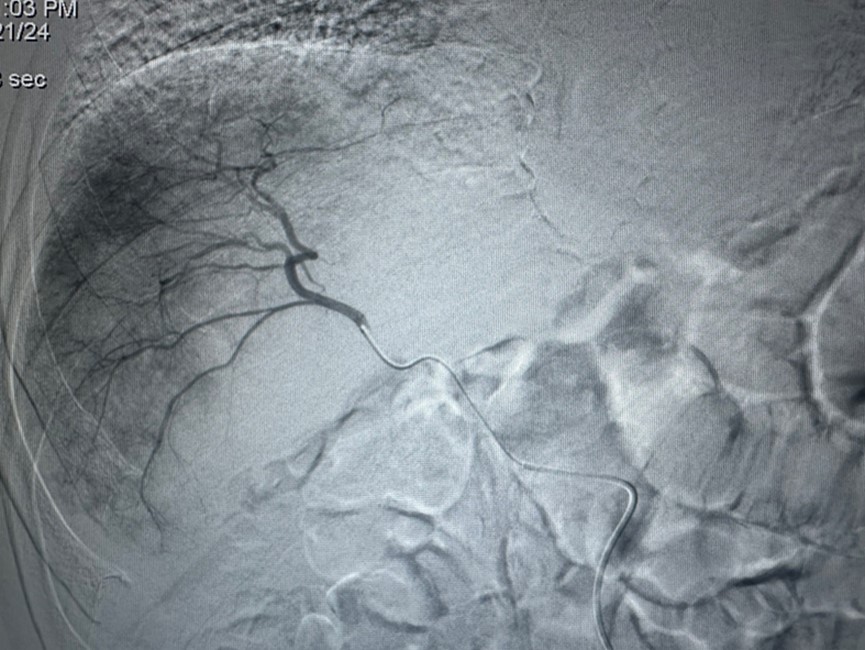

图1:HAIC术中将导管超选择至肿瘤供养血管